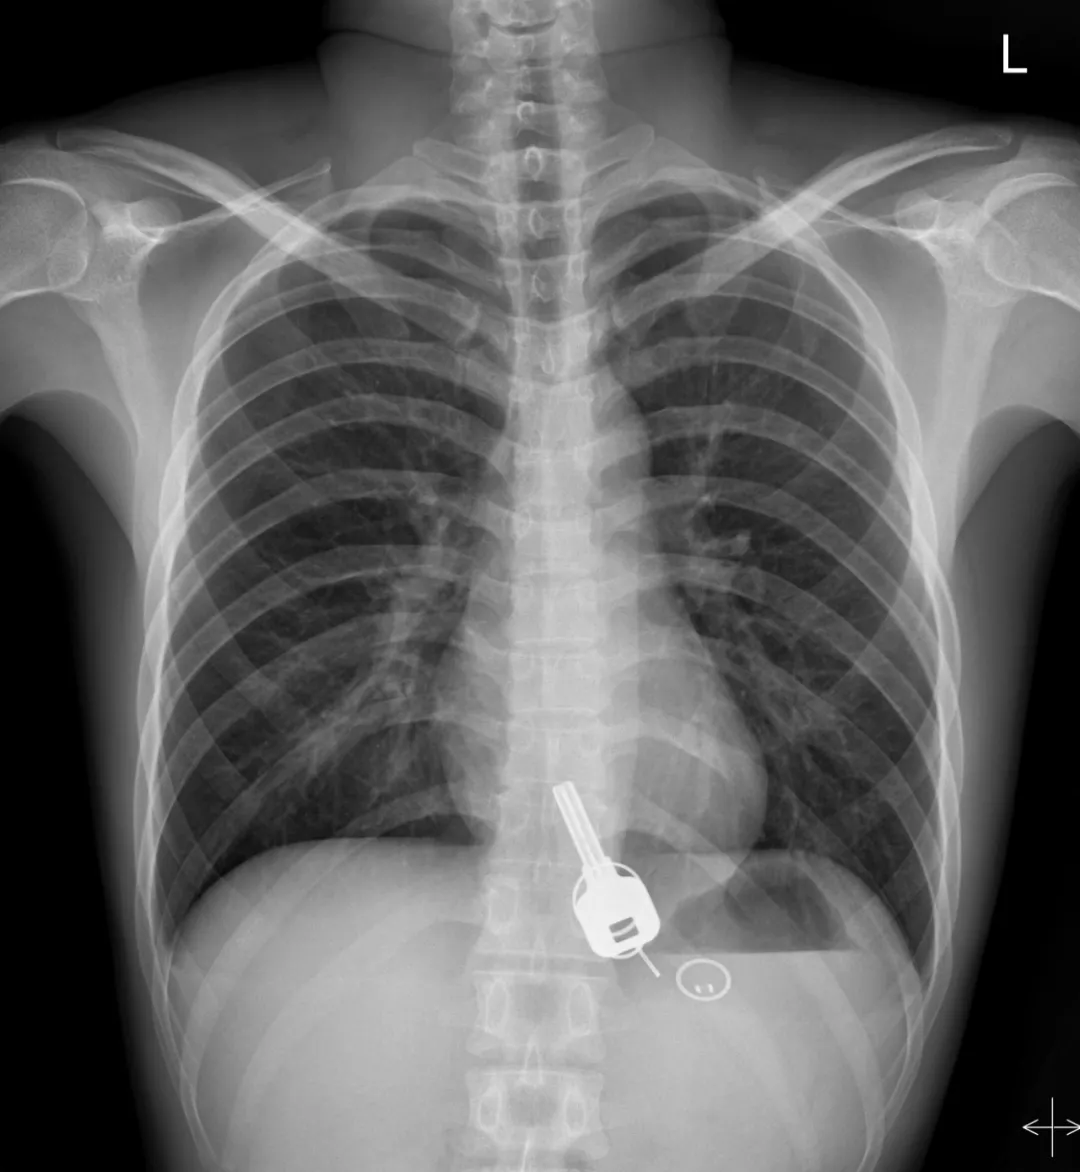

而下面東莞小哥喝酒喝到吞鑰匙

廣東東莞的常先生酒后回家找不到鑰匙,酒醒后他感到胸口疼痛,去醫(yī)院一查,發(fā)現(xiàn)一把鐵鑰匙、2個(gè)鑰匙扣、1個(gè)門(mén)禁牌清楚顯示在肚子胃區(qū)的位置上。